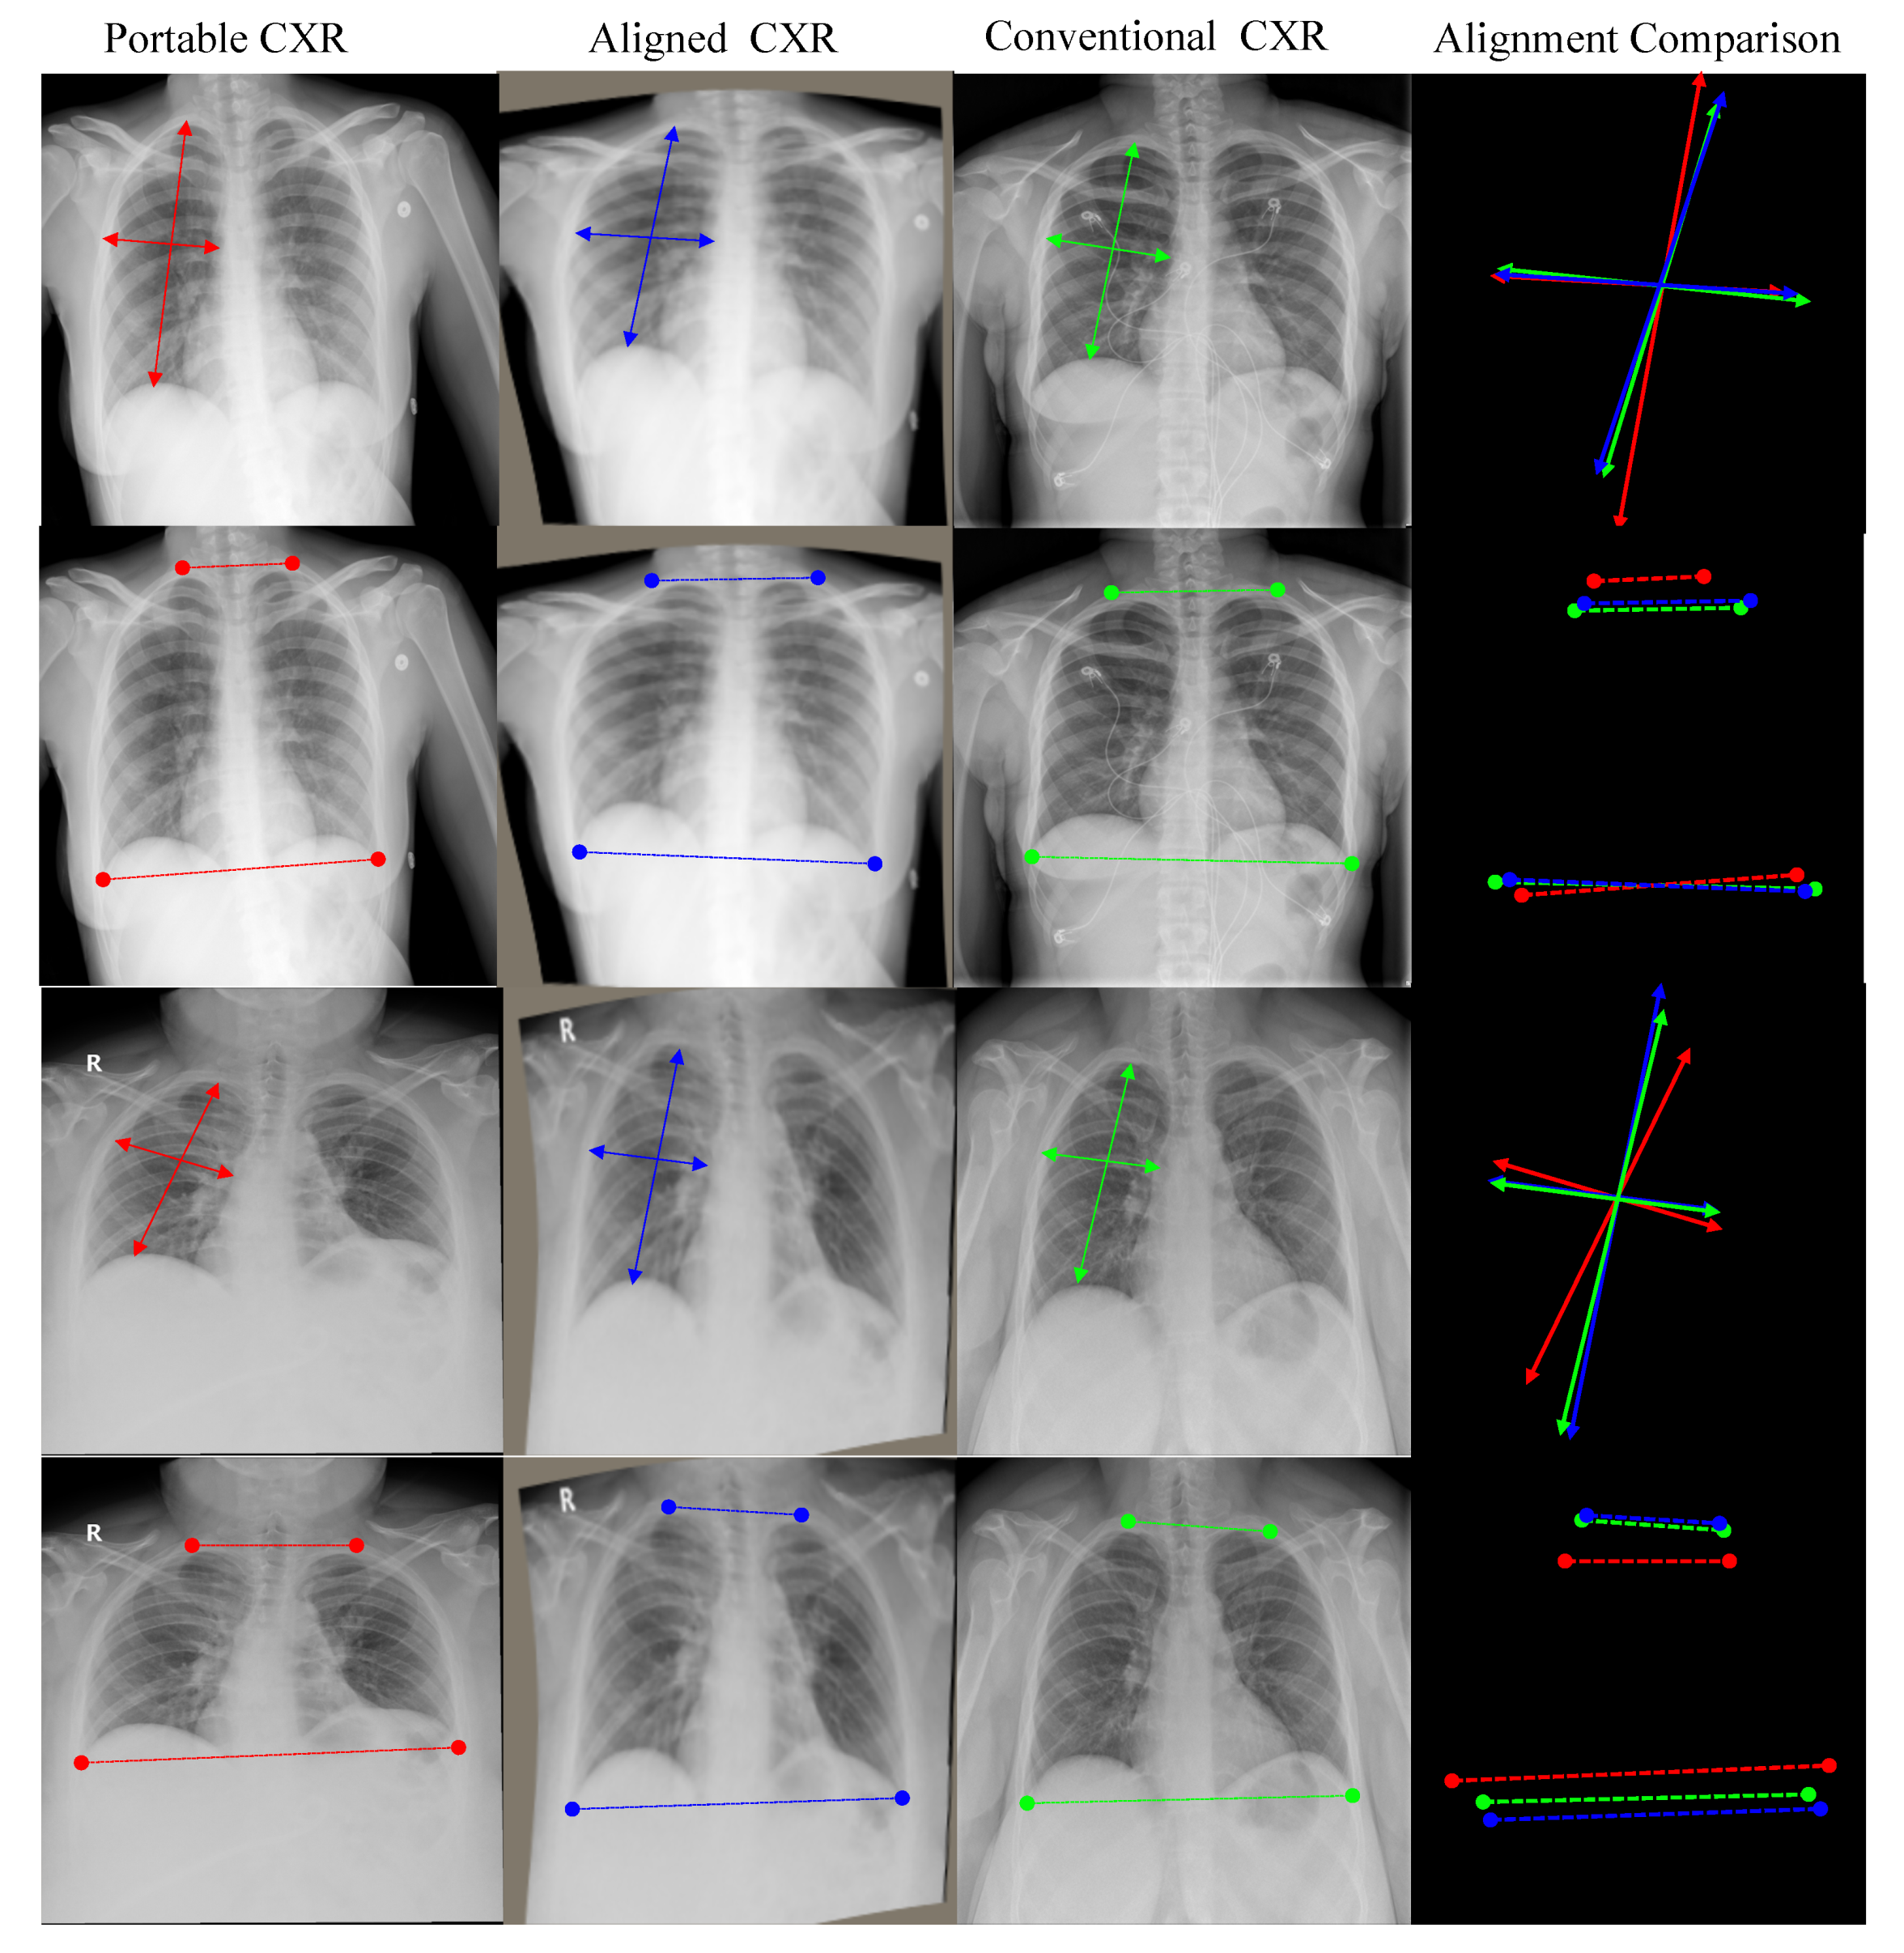

- Secondly, we introduce a new deep learning-based approach to align a subject-pairs dataset to obtain pixel-pairs dataset. In order to learn the knowledge correlation between two different domains, it is important to have a pixel-wise pair dataset. Thus, alignment is an important step that helps to perform knowledge transferring from the source domain to target domain.

3.1. Portable Radiograph Alignment

4.3.1. CXR Alignment Network

| Portable CXR vs. Conventional CXR | Aligned CXR vs. Conventional CXR | |

|---|---|---|

| Left Lung | 203.03 | 42.02 |

| Right Lung | 239.31 | 38.86 |

| Entire CXR | 221.17 | 40.44 |